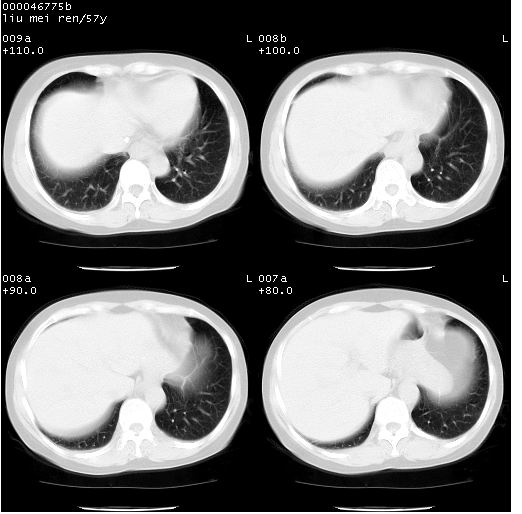

标题: CT12948:鉴赏一下——上腔静脉变异(CT平扫表现)。

患者 女,57岁。因车祸受伤,其家属要求行“全身ct检查”。平素健康。

胸部ct轴位平扫(层厚10mm,螺距1.5,重建间隔10mm),图像如下:

左位上腔静脉,先天变异。

左位上腔静脉,先天变异。与双侧上腔静脉区别。